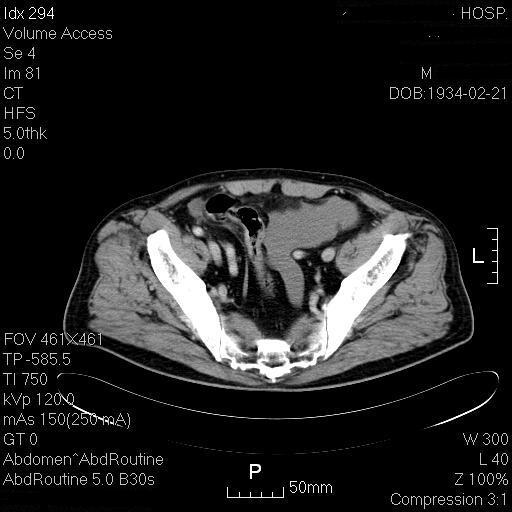

盆腔有积血!!!

腹腔有积血!!!